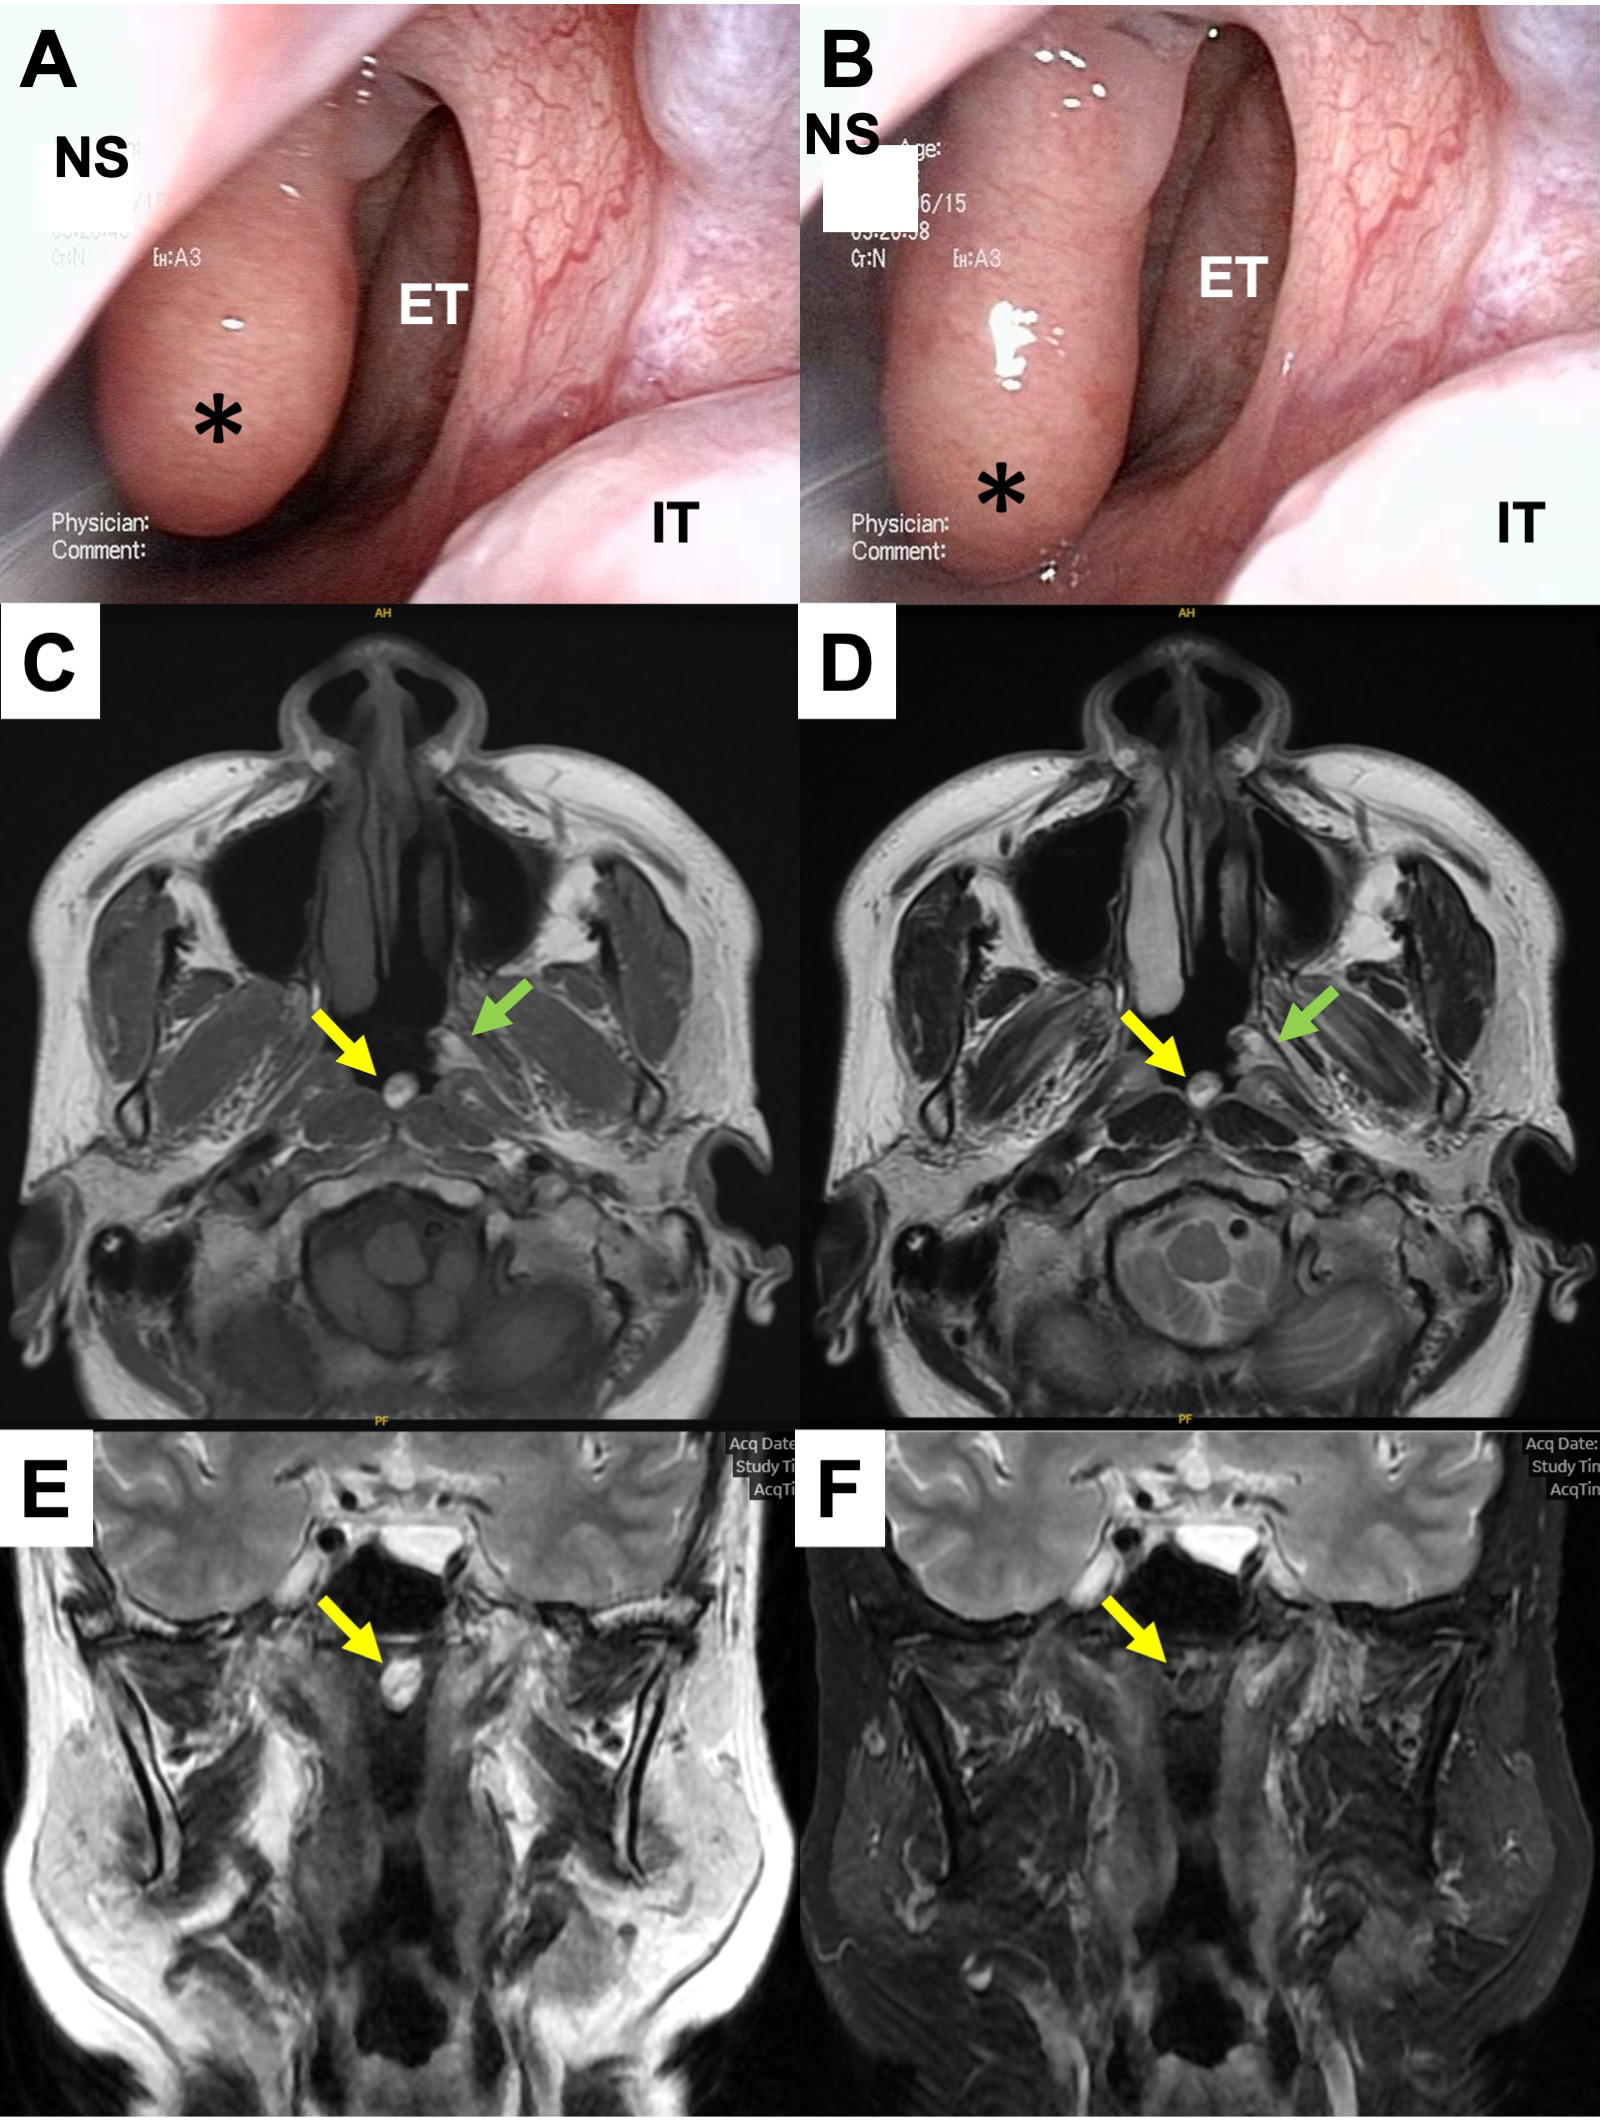

Endoscopic examination at our hospital confirmed two tumors moving in the nasopharynx other than vocal cord polyp. They were located upon the superior wall of the nasopharynx (Figures 1A, B) and the pharyngeal orifice of the Eustachian tube, respectively. They both had smooth surfaces and spontaneously contracted and relaxed without specific stimulation (Supplementary Video 1). Lesions with high intensity and areas of partial low intensity were shown in both T1- and T2-weighted plain magnetic resonance imaging (MRI) (Figures 1C–E). T2-weighted images with fat suppression showed low-intensity signals that were consistent with the tumor sites (Figure 1F).

Figure 1

Preoperative findings. (A, B) Endoscopic findings in the left nasopharynx. A smooth-surfaced tumor originating from the nasopharyngeal superior wall was spontaneously contracting (A) and relaxing (B). *, the tumor; NS, nasal septum; ET, Eustachian tube; IT, inferior turbinate. (C–F) MRI findings at the level of the nasopharynx. The tumor showed high intensity including partial iso intensity in both T1 (C) and T2-weighed images (D, E). In a fat-suppressed image, the intensity of the tumor turned low signal (F).